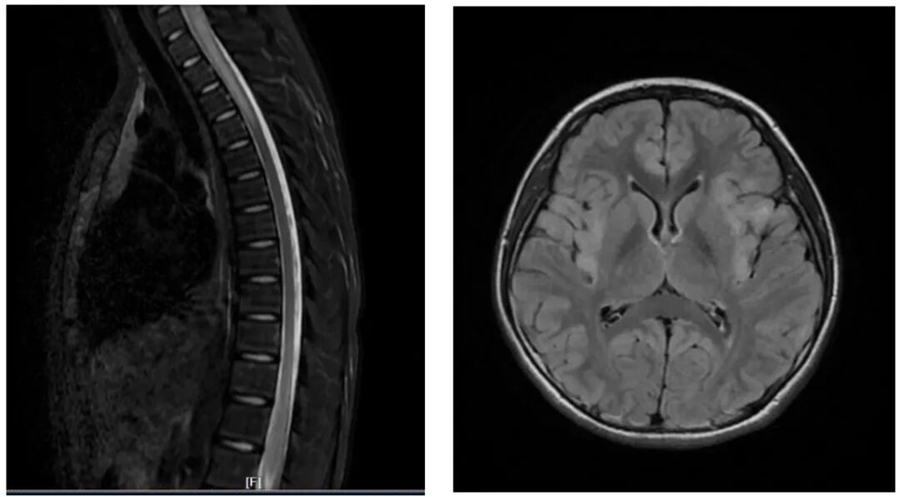

神经内科专家经详细问诊、查体后,当即决定将双双收入院,并安排了血液检查、腰椎穿刺、头颅 + 全脊髓磁共振等一系列检查。最终明确诊断,双双患有中枢神经系统脱髓鞘病。

可能很多家长对这个疾病感到陌生,简单来说,它是一组由自身免疫介导的疾病,主要影响中枢神经系统的白质。我们可以把神经比作“电线”,而髓鞘就是包裹在电线外面的“绝缘层”,当髓鞘受损(脱髓鞘),神经信号的传导就会受到影响,从而引发各种症状。

这类疾病可分为急性播散性脑脊髓炎、MOG 抗体相关疾病、视神经脊髓炎谱系疾病、多发性硬化等不同类型。其临床表现十分复杂多样,常见的有眼痛、视力下降、癫痫、头晕头痛、肢体无力、感觉麻木、二便障碍等,严重时还可能出现意识障碍、呼吸衰竭,甚至危及生命,或遗留严重的神经系统后遗症。